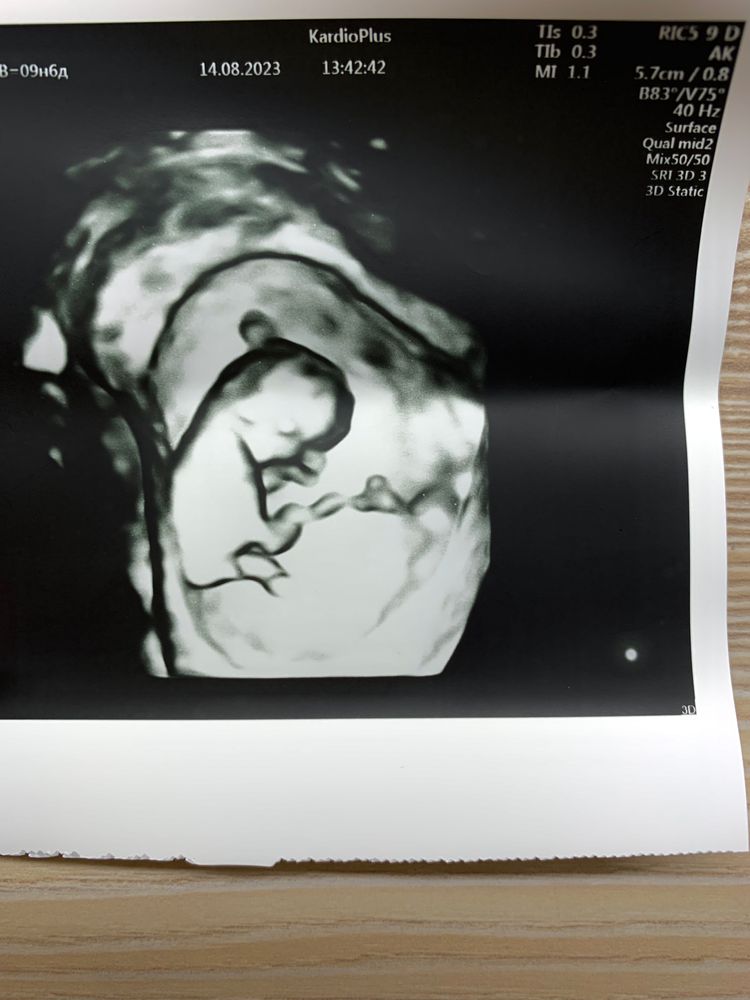

1 мая узи

1 мая узи 100 фото